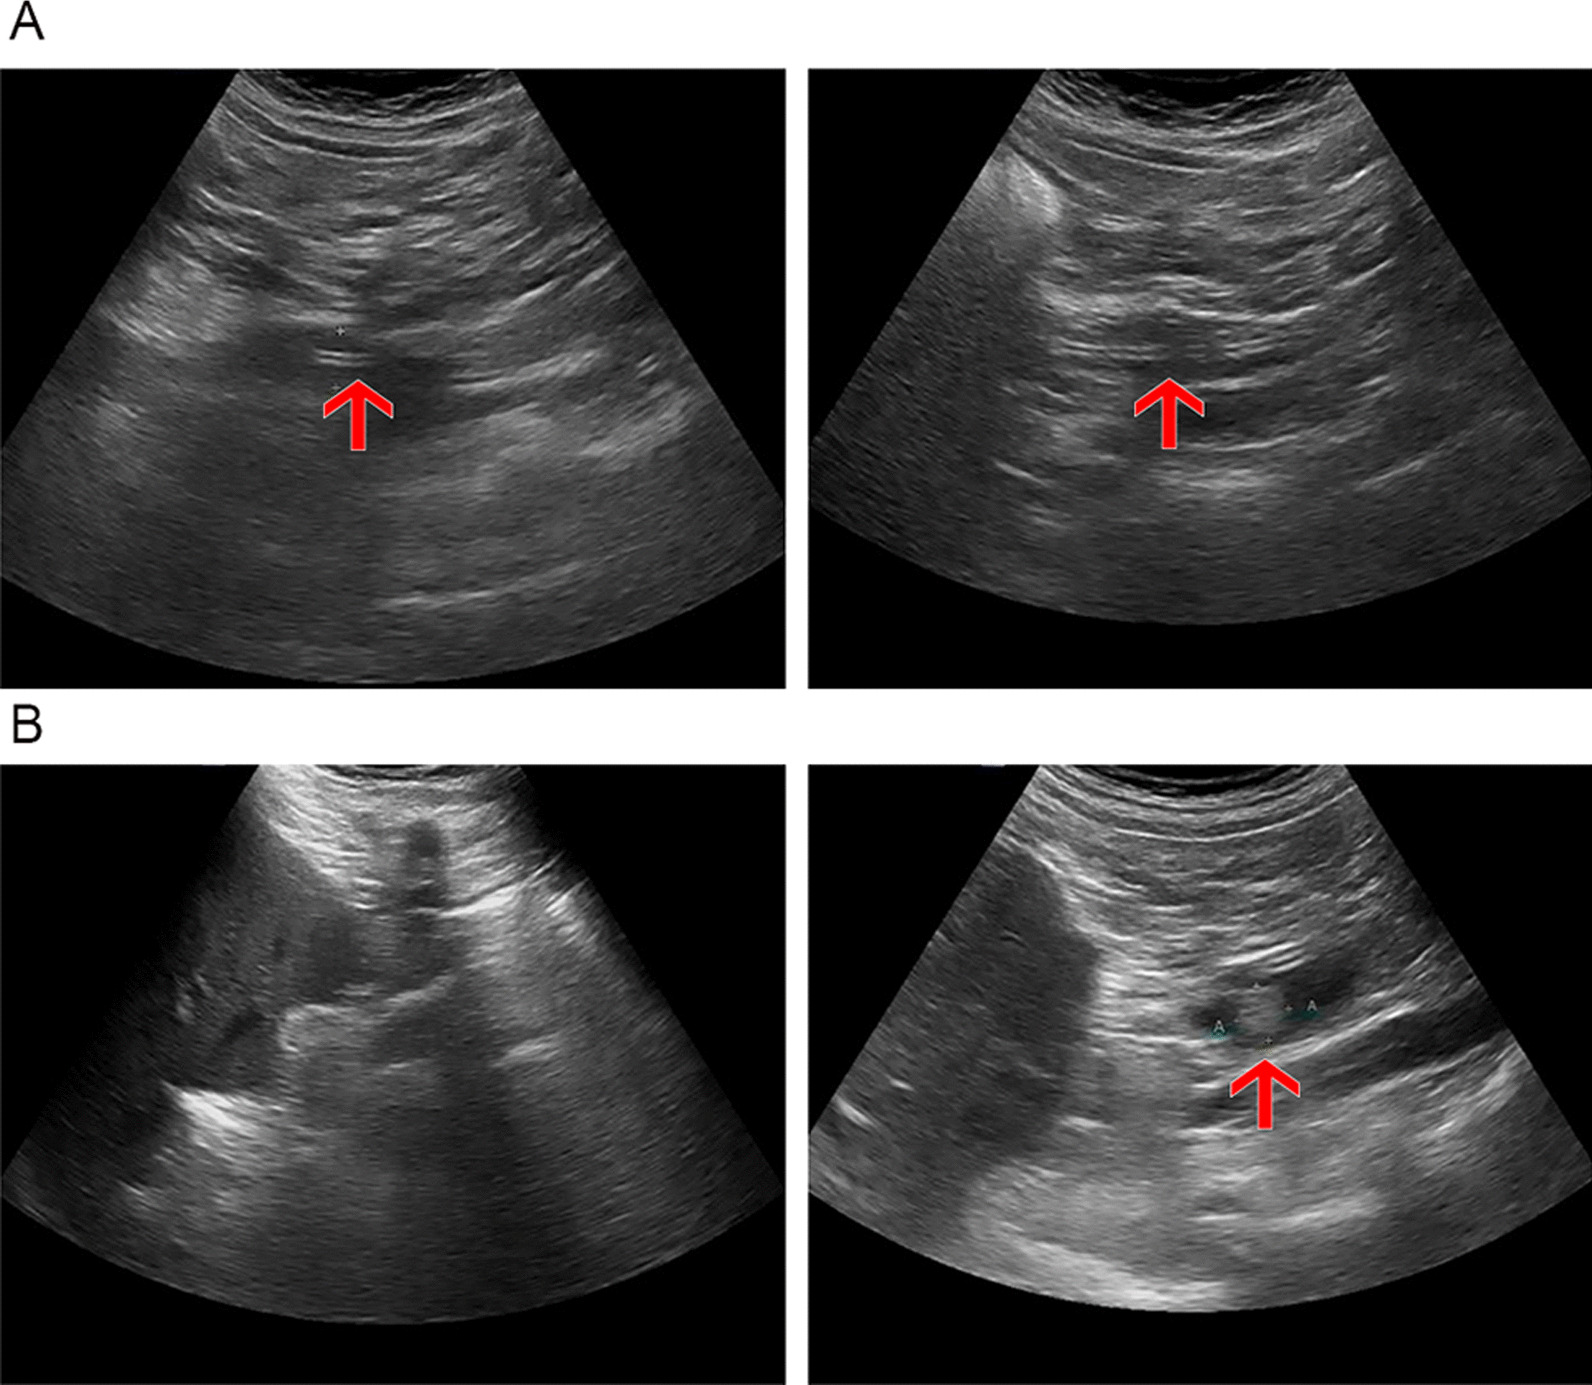

In routine US examinations of the 302 patients studied, there were 12 true positives, 250 true negatives, 1 false positive, and 39 false negatives (specificity, 99.6%; sensitivity, 23.5%; false-positive rate, 0.4%; false-negative rate, 76.5%). Again, ENBD-based saline-injection US significantly outperformed routine US, demonstrating higher sensitivity (p < 0.001) and a lower false-negative rate (p < 0.001), whereas specificities and false-positive rates did not differ significantly (p = 0.249). CBD imaging rates (p < 0.001), lengths (p = 0.048), and diameters (p = 0.034) also differed significantly (Table 3), with higher magnitudes displayed by saline-injection US. A comparison of the imaging effects of routine US and ENBD-based saline US is shown in Fig. 4.

Routine US studies are not very useful for diagnosing choledocholithiasis or assessing a normal CBD. Particularly in the lower CBD segment, interference by the intestinal tract and field gas creates a suboptimal environment. In addition, the sphincter of Oddi is functionally altered after EST, allowing retrograde biliary migration of intestinal gas. The limited space between the ENBD cannulas and the CBD wall hinders ductal visualization, so any small stones harbored within cannot be detected. In this study, the sensitivity of routine US imaging for identifying residual stones was 23.5%, the rate of complete CBD imaging was only 28.8%, and the imaging rate of lower-segment CBD was 45%. Thus, we used a novel approach of injecting saline via ENBD tubes (under US guidance) to disengage the ENBD/CBD interface, creating more space and expelling any biliary tract gas, thereby overcoming the related drawbacks.In this study, among the 289 patients without stones found by routine ultrasound, 38 patients were suspected to have residual stones after ENBD saline injection ultrasound examination, and 34 patients were removed stones during the secondary ERCP or surgical interventions,which indicating that the residual stones of these 34 patients were missed by routine ultrasound and found by ENBD injection ultrasound. US examinations have the advantage of being real-time and dynamic in nature. In our study, patients were regularly placed in left lateral positions, making it easier for retrograde CBD gas to be discharged into the intestinal tract and preventing its return. At the same time, injection of saline served to eliminate gas in the duodenum and enhance delineation of the lower CBD. The results of this study show that, the length and diameter of the common bile duct of ENBD saline injection ultrasound are higher than that of routine ultrasound, which proves that water injection ultrasound can make up for the shortcoming of poor imaging effect of bile duct during routine ultrasound.